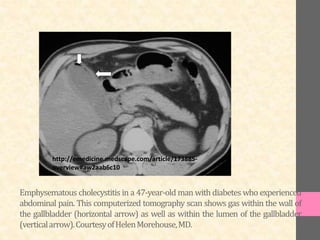

Emphysematous cholecystitis in a 47-year-old man with diabetes who experienced

abdominal pain. This computerized tomography scan shows gas within the wall of

the gallbladder (horizontal arrow) as well as within the lumen of the gallbladder

(verticalarrow).CourtesyofHelenMorehouse,MD.

Emphysematous cholecystitis ina 47-year-old man with diabetes who experienced abdominal pain. This computerized tomography scan shows gas within the wall of the gallbladder (horizontal arrow) as well as within the lumen of the gallbladder (verticalarrow).CourtesyofHelenMorehouse,MD. http://emedicine.medscape.com/article/173885- overview#aw2aab6c10